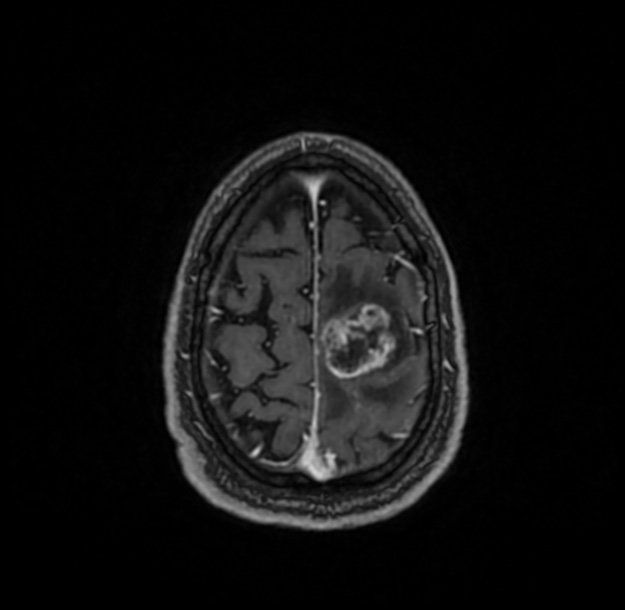

TUMORES CEREBRALES

Un tumor cerebral es una colección anormal de células que crece en, o alrededor del, cerebro. Presenta un riesgo para el cerebro sano porque invade o destruye el tejido normal del cerebro comprimiéndolo y desplazando al cerebro.